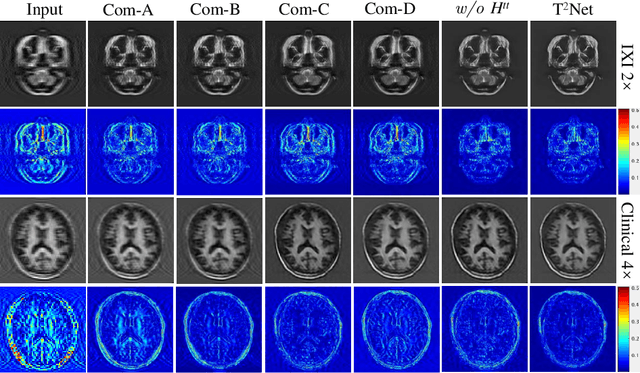

The core problem of Magnetic Resonance Imaging (MRI) is the trade off between acceleration and image quality. Image reconstruction and super-resolution are two crucial techniques in Magnetic Resonance Imaging (MRI). Current methods are designed to perform these tasks separately, ignoring the correlations between them. In this work, we propose an end-to-end task transformer network (T$^2$Net) for joint MRI reconstruction and super-resolution, which allows representations and feature transmission to be shared between multiple task to achieve higher-quality, super-resolved and motion-artifacts-free images from highly undersampled and degenerated MRI data. Our framework combines both reconstruction and super-resolution, divided into two sub-branches, whose features are expressed as queries and keys. Specifically, we encourage joint feature learning between the two tasks, thereby transferring accurate task information. We first use two separate CNN branches to extract task-specific features. Then, a task transformer module is designed to embed and synthesize the relevance between the two tasks. Experimental results show that our multi-task model significantly outperforms advanced sequential methods, both quantitatively and qualitatively.